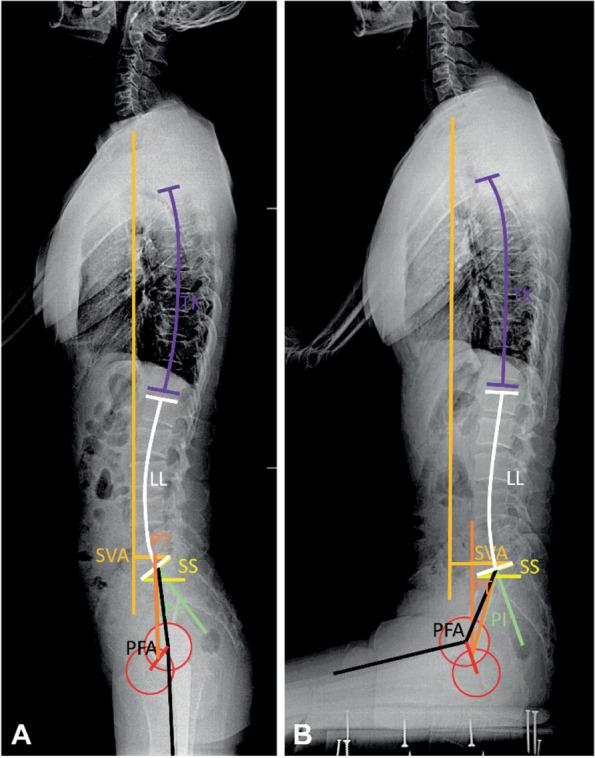

We conducted a retrospective review of consecutive primary THA patients. We measured SVA, spinopelvic parameters (pelvic tilt [PT], pelvic incidence, and sacral slope), thoracic kyphosis (TK), lumbar lordosis (LL), proximal femur angle (PFA), and cup version using functional radiographs of patients in the standing and upright sitting positions. Linear regression was performed to identify parameters related to global trunk alignment change (∆SVA). Spinopelvic stiffness was defined as PT position change < 10°, and a subset of patients with PT change < 0° was categorized into a paradoxical spinopelvic motion group.

One hundred twenty-four patients were analyzed (mean age: 65 years, 61% female). In univariate regression analysis, ∆TK, ∆LL, and ∆PFA were correlated to ∆SVA. In multivariate regression analysis, ΔLL (p < 0.001) and ΔPFA (p < 0.001) were found to be correlated to ΔSVA (ΔSVA = - 11.97 + 0.05ΔTK - 0.23ΔLL - 0.17ΔPFA; adjusted R = 0.558). Spinopelvic stiffness was observed in 40 patients (32%), including five (4%) with paradoxical motion (∆PT = - 3° ± 1°, p < 0.001) with characteristics of balanced standing global trunk alignment (standing SVA = - 1.0 ± 5.1 cm), similar stiffness of the lumbosacral spine (∆LL = - 7° ± 5°), higher hip motion (∆PFA = - 78° ± 6°, p = 0.017), and higher anterior trunk shift (∆SVA = 6.2 ± 2.0 cm, p = 0.003) from standing to sitting as compared to the stiffness group. Two of these five patients experienced dislocation events after THA.

The lumbosacral and hip motions were the major contributors to global alignment postural change. Paradoxical motion is a rare but dangerous clinical condition in THA that might be related to a disproportionally large trunk shift in the stiff lumbosacral spine causing excessive hip motion. In paradoxical motion, diminishing functional acetabular clearance during position change might pose the prosthesis at higher risk of impingement and instability than spinopelvic stiffness.

我们对连续的原发性 THA 患者进行了回顾性研究。我们测量了站立位和直立坐姿位时 SVA、脊柱骨盆参数(骨盆倾斜度[PT]、骨盆入射角和骶骨倾斜度)、胸腰椎后凸角(TK)、腰椎前凸角(LL)、股骨近端角(PFA)和杯倾斜度。使用线性回归来确定与整体躯干对线变化(ΔSVA)相关的参数。脊柱骨盆僵硬度定义为 PT 位置变化<10°,PT 变化<0°的亚组患者被归类为反常脊柱骨盆运动组。

共分析了 124 例患者(平均年龄:65 岁,61%为女性)。在单变量回归分析中,ΔTK、ΔLL 和 ΔPFA 与 ΔSVA 相关。在多变量回归分析中,ΔLL(p<0.001)和 ΔPFA(p<0.001)与 ΔSVA 相关(ΔSVA=-11.97+0.05ΔTK-0.23ΔLL-0.17ΔPFA;调整后的 R=0.558)。40 例(32%)患者出现脊柱骨盆僵硬,其中 5 例(4%)出现反常运动(ΔPT=-3°±1°,p<0.001),具有平衡的站立位整体躯干对线特征(站立位 SVA=-1.0±5.1cm),腰骶脊柱僵硬度相似(ΔLL=-7°±5°),髋关节活动度更高(ΔPFA=-78°±6°,p=0.017),从站立位到坐位时,前躯干移位更大(ΔSVA=6.2±2.0cm,p=0.003)。这 5 例患者中有 2 例在 THA 后发生了脱位事件。

腰骶部和髋关节运动是导致整体对线姿势变化的主要因素。反常运动是 THA 中一种罕见但危险的临床情况,可能与僵硬的腰骶脊柱中躯干过度移位导致髋关节活动度过大有关。在反常运动中,在位置变化过程中功能髋臼间隙减小可能会使假体面临更高的撞击和不稳定风险,而不是脊柱骨盆僵硬。